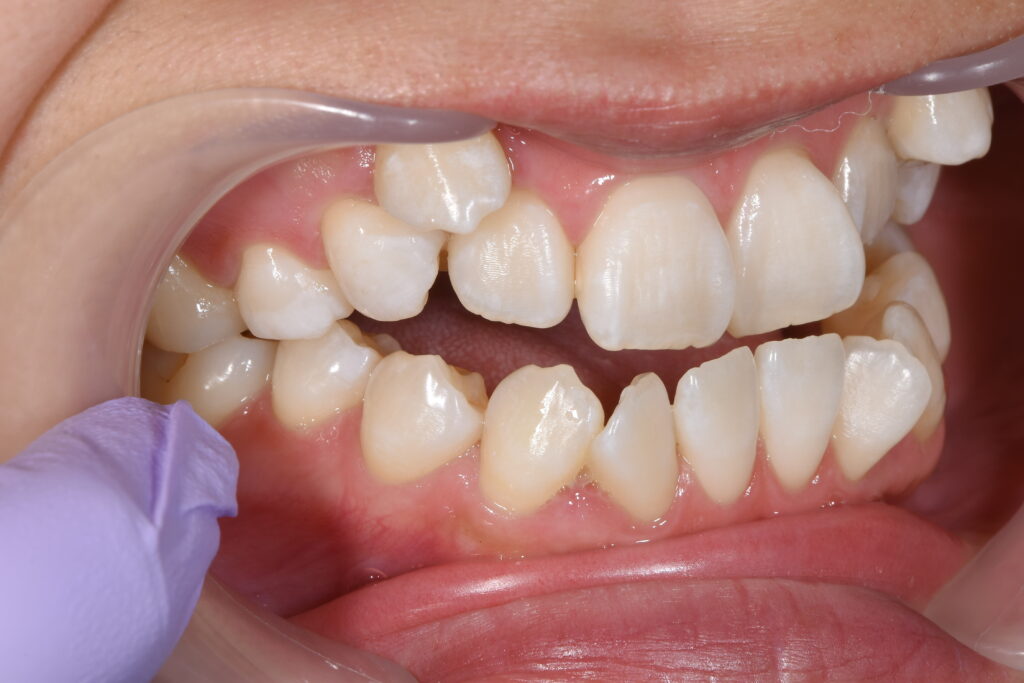

まずは初診時です。

【初診時】

今回ご紹介の患者様の問題点

①叢生(歯のがたつき)→清掃性が悪く将来虫歯・歯周病リスクが高くなる

②開口(奥歯しか噛んでいない)→かみ合わせが原因で、将来的に奥歯が痛くなる

③審美的問題

以上の問題点より、矯正治療を開始致しました。

今回の治療計画は上下小臼歯の抜歯を行いました。

治療装置はインビザライン(マウスピース)です。針金は使用しておりません。